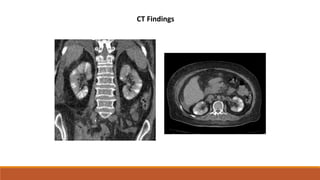

the thrombosis is observed as a

filling defect during venous

phase imaging following

intravenous contrast

Long linear filling defect in the left renal vein.

CT findings